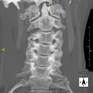

Cervical spine CT

Radiological test that provides high definition anatomical images of the cervical vertebrae using CT (Computed Tomography) equipment. Indicated for: neck pain with or without radiation to the arms, trauma, congenital malformations.